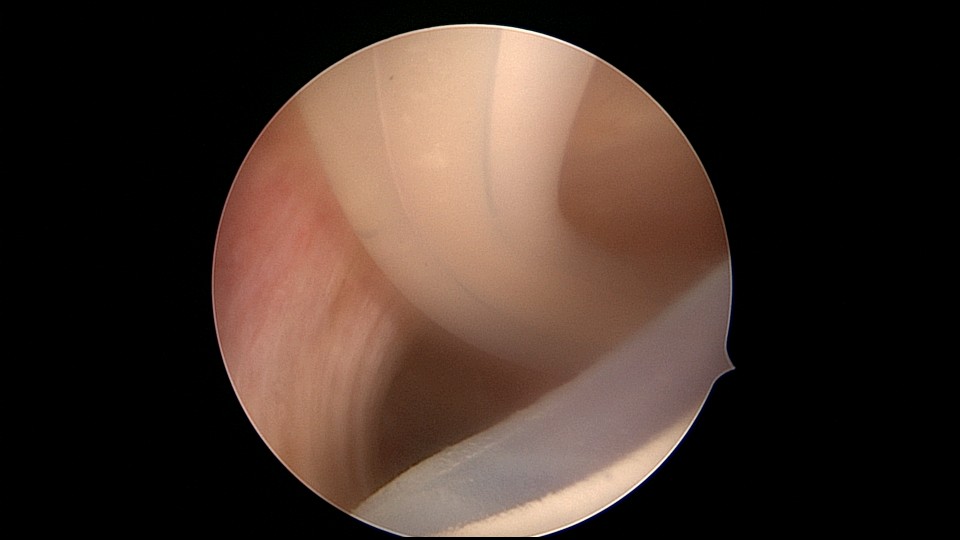

患者32岁,G10P1,剖宫产1次。2020年2月人流术后闭经2+月,2020年5月宫腔镜探查见剖宫产切口憩室,宫颈内口以上广泛封闭粘连,AFS评10分,双极电针分粘效果差,扩张宫颈管,改用双极电切分粘,恢复宫腔形态,显露双侧输卵管开口。2020年6月宫腔镜二探取球囊,宫腔形态正常,双侧输卵管开口可见。2020年10月自然妊娠,2021年2月初的某一天,在电梯里,病人的老公认出我是给他老婆做手术的医生,表达感谢之余,讲病人因先兆流产在产科保胎,情绪不稳定,甚至想终止妊娠,医生及家属努力安抚病人。2021年5月,36+3周剖宫产分娩。现37岁,G11P2。